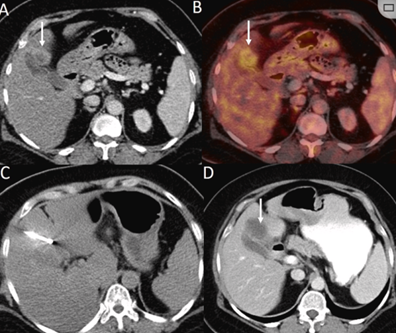

79 歲男性,肝轉移(結直腸癌)腫瘤的完全消融病例

( a ) 軸向 MRI 和 ( b ) 軸向 CT 顯示肝S8段有一個16mm的病灶,鄰近肝緣。

( c )冷凍消融期間CT顯示放置了2個冷凍探針,低密度冰球包圍病灶。

(d)術后1個月隨訪 CT顯示冰球對應的壞死區(qū)域,未見復發(fā)。

(e)術后6個月的CT,壞死區(qū)域縮小,未見復發(fā)。

(f)與基線影像(g)相比,12個月后的FDG-PET/CT顯示未見FDG攝取。

undefined

62歲女性,肝轉移(卵巢癌)腫瘤的完全消融病例

(a)軸向CT顯示病變位置毗鄰心臟和上腔靜脈(黑色箭頭)。

(b)術中軸向CT掃描:使用三個冷凍探針。

(c)冠狀面和(d)矢狀面顯示冰球毗鄰心包。

1個月后的軸向(e)和冠狀位(f)增強CT掃描顯示低密度區(qū)域,由于肉芽組織反應引起的邊緣增強。